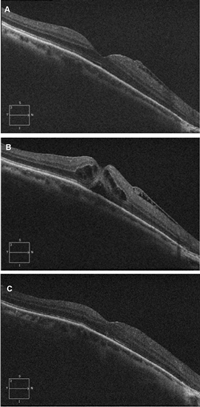

En formas recientes de agujero macular puede verse conservación de la capa elipsoide y de la membrana limitante interna en los bordes del agujero (

Figura 7). En formas con una mayor cronicidad suele perderse la integridad de la capa elipsoide y de la membrana limitante externa, aparece un levantamiento de los bordes con un edema quístico en los márgenes del agujero y se aprecian alteraciones del epitelio pigmentario (

Figura 7. Agujero macular de reciente aparición. Se objetiva un defecto completo de todas las capas de la retina. Es posible apreciar con claridad la membrana limitante interna (flechas blancas) y la capa elipsoide (flechas rojas) en los márgenes del agujero.

Figura 8. Agujero macular crónico. Se aprecia un levantamiento de los bordes del agujero, con edema quístico. En los márgenes del agujero no pueden diferenciarse la membrana limitante interna y la capa elipsoide.